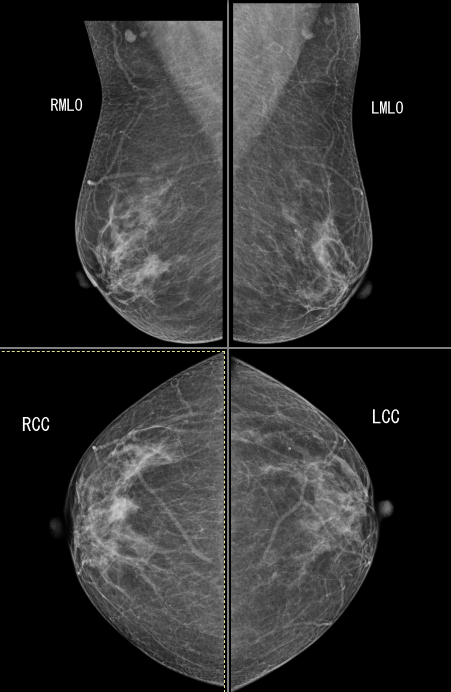

2021-7-14乳腺钼靶:右乳中央区略偏下见一约13.4mmx14mm稍高密度结节,形态欠光整,边缘见毛刺影。考虑BI-RADS4c类。

??图2.乳腺钼靶